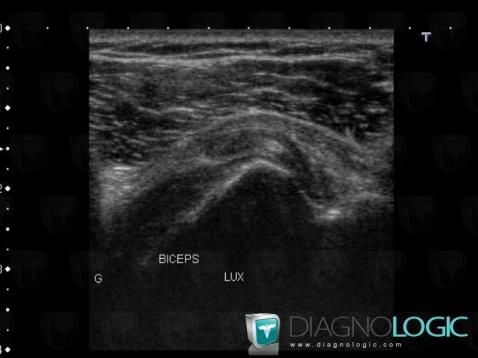

The images below illustrate this case for diagnoses Dislocation of the biceps brachii tendon, for the modalities (US)

- Diagnosis Dislocation of the biceps brachii tendon, Location(s) Long head of biceps tendon, with gamuts